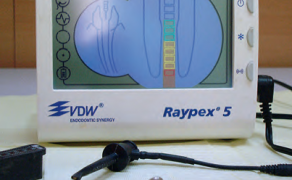

Streszczenie: Zastosowanie mikroskopu zabiegowego, mikroinstrumentów, narzędzi ultradźwiękowych i materiałów zaawansowanych biotechnologicznie zrewolucjonizowało tradycyjne techniki chirurgii endodontycznej. Przypadki endodontyczno-chirurgiczne klasy A, B i C predysponują do leczenia zachowawczego lub mikrochirurgicznego i w większości przypadków kończą się powodzeniem, w odróżnieniu od klas: D, E i F. Właściwe i skuteczne ich leczenie wymaga endodontycznych technik mikrochirurgicznych oraz sterowanej regeneracji tkanek.

Summary: Microscope, microsurgical instruments, ultrasonic instruments and advanced biotechnological materials has revolutionized traditional techniques in endodontic surgery. Class A, B and C of the clinical classification of endodontic-microsurgical cases predispose to conservative or microsurgery treatment and in most cases are successful. Cases D, E and F class are more difficult. Proper and effective treatment requires endodontic microsurgical techniques and guided tissue regeneration.

Mikrochirurgia endodontyczna to dział stomatologii wywodzący się z chirurgii endodontycznej (endodoncja chirurgiczna). Głównym jego celem jest diagnozowanie i leczenie zmian pochodzenia [...]